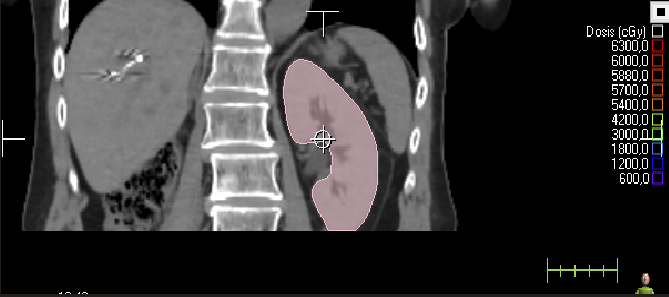

Abdomen

Contorneos

8